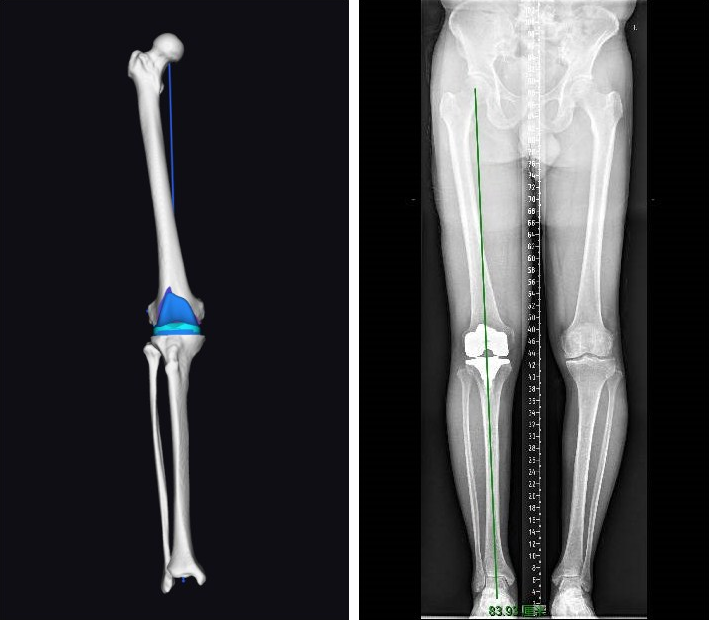

术前,赵宇驰团队与机器人工程师团队进行了充分讨论,并导入患者的下肢CT影像学数据,在术前规划系统中模拟截骨量,假体大小型号、内外侧间隙等情况。由于多次的术前假体骨操作准备充分,术中骨面90多个注册点一次性通过,减少了非必要的重复操作,为手术节约了宝贵时间。术中也无需股骨髓内定位杆,减少了髓腔内出血。截骨量也对传统的“股骨9mm-胫骨10mm”进行了个性化调整。最终,术中假体型号、垫片厚度以及截骨量与术前完全一致,下肢力线也由术前的内翻8°恢复到0°。虽然前期的准备工作相对较多,但是各团队之间默契配合,手术过程仍然比较顺利,首台机器人辅助全膝关节置换术在一个止血带的时间之内就完成了假体植入。积累了经验之后,第二台手术的假体植入时间缩短至68 分钟。两台手术的术中出血量均在 100ml 以内。术中运动轨迹良好,力线恢复与术前规划模拟一致。

术后力线与术前规划一致。